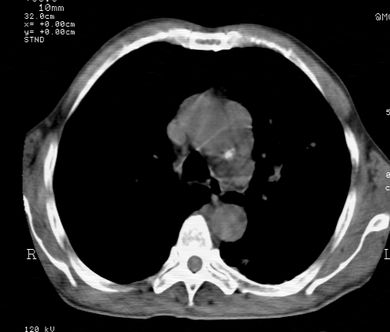

标题: CT24000:M65,胸痛,胸闷月余,既往慢支,肺气肿,肺心病 [打印本页]

标题: CT24000:M65,胸痛,胸闷月余,既往慢支,肺气肿,肺心病

左肺门肿块,相应支气管闭塞,左肺上叶、舌叶大片及散在高密度影,部分呈不张改变,两肺纹粗乱,左侧胸腔积液。考虑左侧中央型肺癌伴阻塞性改变。

左肺门见巨大软组织肿块影,直径约--,境界清,左上肺叶支气管变窄,左上肺舌叶见大片状密实影,余肺纹理增多、紊乱、纤细、部分网格状,两肺透亮度增高,纵隔内见增大多发淋巴结影,心影略左偏,左侧少量胸腔积液。

左侧中央型肺癌伴左上肺舌叶不张、纵隔淋巴结转移,左侧少量胸腔积液。